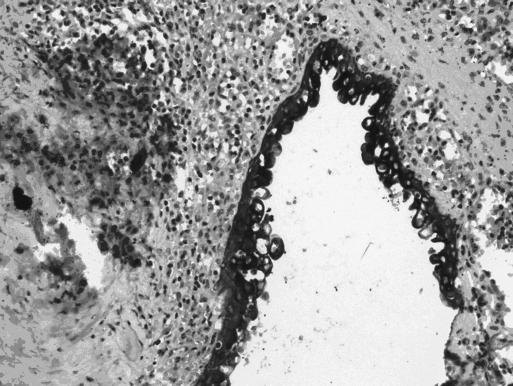

True nonparasitic splenic cysts are rare. Reports of approximately 30 cases of benign true splenic cysts producing elevated CA 19-9 serum levels have been published. The traditional treatment of splenic epidermoid cysts is splenectomy. However, with all the advances in laparoscopic surgery, conservative laparoscopic approaches are accepted as the most preferred techniques for this benign disease. Laparoscopic cystectomy with its minimal invasiveness and low morbidity is the ideal technique for properly selected patients. So far, only one case report of laparoscopic cystectomy for splenic epidermoid cyst with elevated CA 19-9 levels has been published. This is the second known report of this procedure being performed to remove a splenic epidermoid cyst in a patient with elevated CA 19-9 levels.

真性非寄生虫性脾囊肿较为罕见。已发表了约30例良性真性脾囊肿导致血清CA 19-9水平升高的报告。脾表皮样囊肿的传统治疗方法是脾切除术。然而,随着腹腔镜手术的所有进展,保守的腹腔镜手术方法被认为是治疗这种良性疾病的最优选技术。具有微创性和低发病率的腹腔镜囊肿切除术是为适当选择的患者的理想技术。到目前为止,仅发表了一例腹腔镜囊肿切除术治疗CA 19-9水平升高的脾表皮样囊肿的病例报告。这是该手术用于切除CA 19-9水平升高患者的脾表皮样囊肿的第二例已知报告。